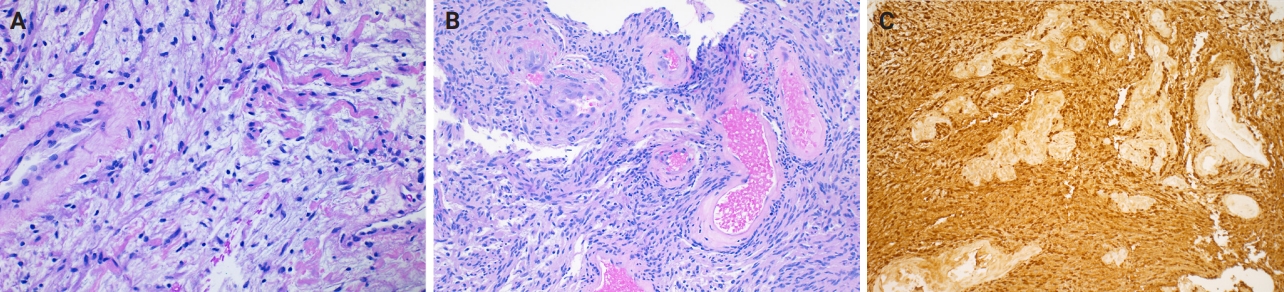

- On mammography, schwannomas present as a well-circumscribed, oval shaped, hyperdense nodule without microcalcifications (Fig. 1A). Ultrasound demonstrates a round/oval, well-circumscribed, homogenous, hypoechoic nodule with parallel orientation (Fig. 1B) [11,12]. Although not routinely performed, magnetic resonance imaging (MRI) is another modality to examine breast schwannomas. MRI T1 demonstrates a low signal and isointense nodule, while MRI T2 demonstrates a heterogeneous hyperintense signal with strong homogeneous contrast enhancement [13].

Fig. 1.Mammogram with a well-circumscribed oval mass with equal density. The arrow indicates the lesion (A). Ultrasound with an oval hypoechoic mass with well-circumscribed margins (B).